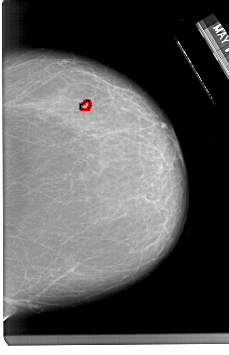

A_1333_1.LEFT_MLO

LEFT_MLO LINES 6541 PIXELS_PER_LINE 4306 BITS_PER_PIXEL 12 RESOLUTION 43.5 NON_OVERLAY

FILE: A_1333_1.RIGHT_CC.OVERLAY

TOTAL_ABNORMALITIES 1

ABNORMALITY 1

LESION_TYPE CALCIFICATION TYPE PLEOMORPHIC DISTRIBUTION CLUSTERED

ASSESSMENT 4

SUBTLETY 2

PATHOLOGY BENIGN

TOTAL_OUTLINES 1

BOUNDARY